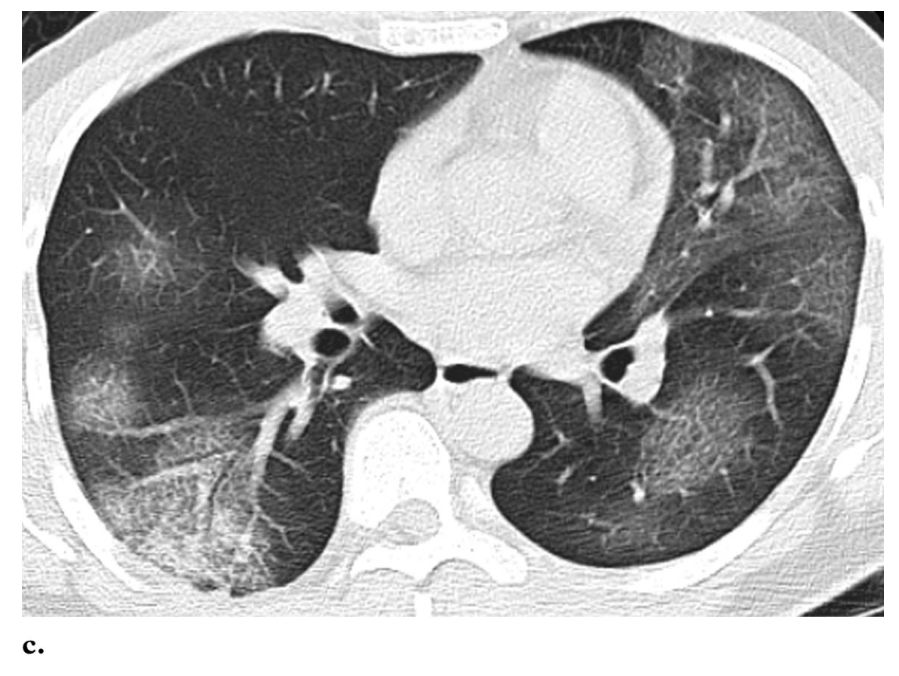

▎病灶分布

病灶主要分布在胸膜下,与胸膜几乎平行,是这次新冠肺炎最具特色的影像学表现。

片状磨玻璃阴影,以胸膜下分布为主。注意,病灶与胸膜大约平行。

图20

总之,不管什么病灶,都是以胸膜下分布为主。

图23